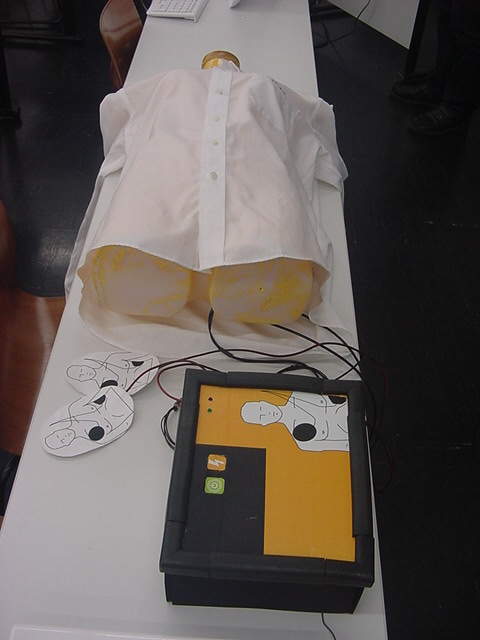

AED

- 展示発表 「メディア造形総合演習II」作品

- 作家 大塚理絵 メディア造形学科4回生

- 概要 卒業制作でAEDを用いた「どきどき」エンタテイメント作品を制作するための予備ステップとして制作した、実際のAEDと同等の操作を体験するインスタレーション作品。電源スイッチを入れ、音声ガイドの指示に従って人体人形の正しい位置に電極を貼付けると電撃ショックを与えるボタンを押す指示が出る

- システム Max/MSP、Gainer、磁気センサ

- 写真 ★

- プレゼン